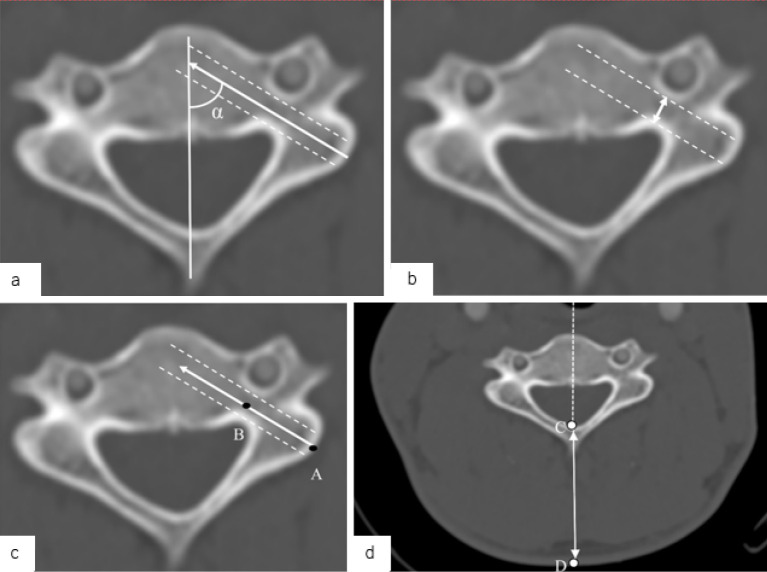

Methods: A retrospective analysis of 36 patients who underwent posterior cervical fusion surgery with CPS placement was conducted using preoperative computed tomography (CT)-based navigation. Cases with CPS insertion at C1 or C2 were excluded. The key morphological parameters-optimal screw trajectory angle, pedicle diameter, and distance from the entry point to the pedicle isthmus (DEP)-were measured on preoperative CT images. CPS placement accuracy was assessed postoperatively using Neo's classification. The receiver operating characteristic (ROC) curve analysis determined the cutoff values for predicting CPS perforation.

Results: Among the 102 CPSs placed from C3 to C7, the overall perforation rate was 25.5%. C3 had the highest perforation rate (45.5%), whereas C7 had the lowest (3.1%). The vertebrae with CPS perforation exhibited a significantly larger optimal screw trajectory angle (45.5° vs. 38.0°, p<0.001), smaller pedicle diameter (4.2 mm vs. 5.2 mm, p<0.001), and longer DEP (13.2 mm vs. 11.9 mm, p=0.002). The ROC analysis identified the following cutoff values: 44.0° for the optimal angle, 4.35 mm for the pedicle diameter, and 12.7 mm for the DEP. These morphological parameters strongly predicted the risk of CPS perforation.